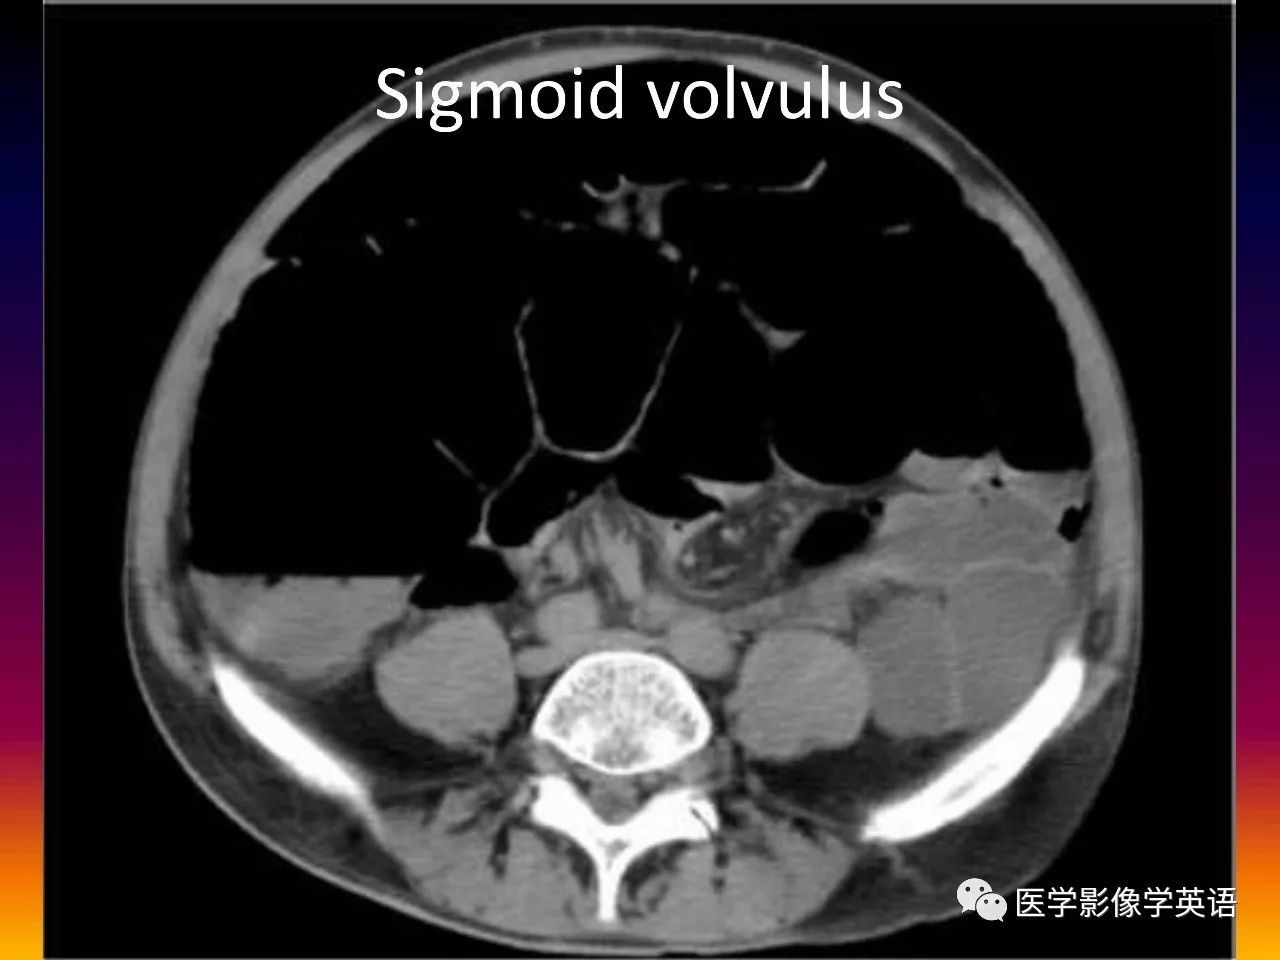

85. Sigmoid volvulus

86. Sigmoid volvulus

87. Sigmoid volvulus

88. Sigmoid volvulus

89. Sigmoid volvulus

90. Sigmoid volvulus

91. Sigmoid volvulus

92. Sigmoid volvulus